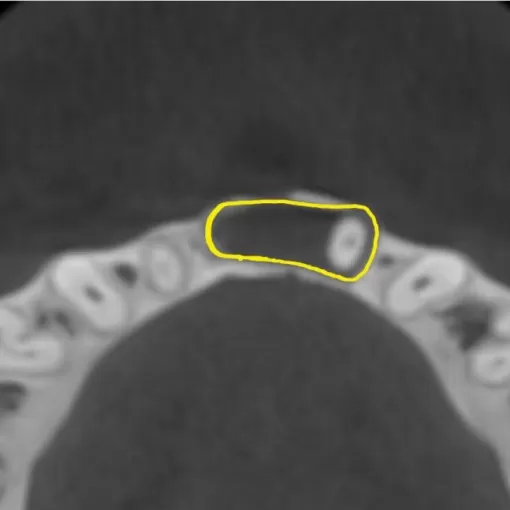

Пациент обратился с целью имплантации в области отсутствующего зуба 4.6. Однако после КЛКТ (3Д) исследования был обнаружен воспалительный процесс (киста) в области соседнего зуба 4.7 (рис. 1).